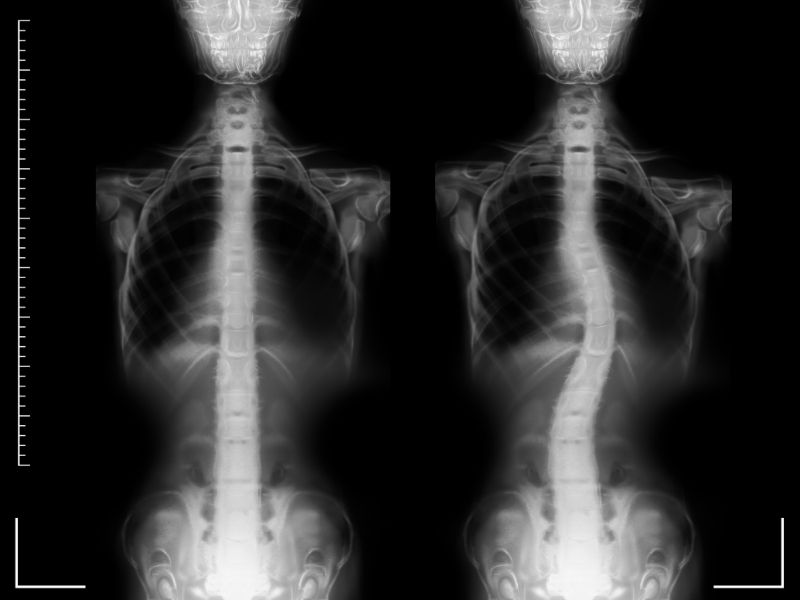

Tanı rontgen ile teyid edilir. Burada skolyozu tam değerlendirmek için ortoröntgenogram denilen tüm omurgayı gösteren filmler kullanılmalıdır. Bu filmlerde eğriliğin bölgesi ve derecesi değerlendirilir. İlerleme riski olan vakalarda 3-6 ay aralıklarla iskelet gelişimi tamamlanana kadar rontgen tetkiki yinelenmelidir.

Omurganın yanlara doğru "S" veya "C" biçiminde kıvrılmasıdır. Bunun sonucunda omurga döner ve bir omuz ve bir kalça diğerinden yüksek görünür. Genetik olanları varsa da genellikle çoğunun nedeni bilinmemektedir. (idiopatik skolyoz)

Skolyoz büyümenin devam ettiği buluğ çağı boyunca hızlı bir ilerleme gösterir. İskelet gelişiminin tamamlanıp büyümenin durduğu yaşlarda ilerleme ileri eğrilikler hariç durur. 50 derece özelliklede 70 derece üzeri eğrilikler erişkin yaşlarda oldukça az olmasına karşı ilerleme gösterirler.